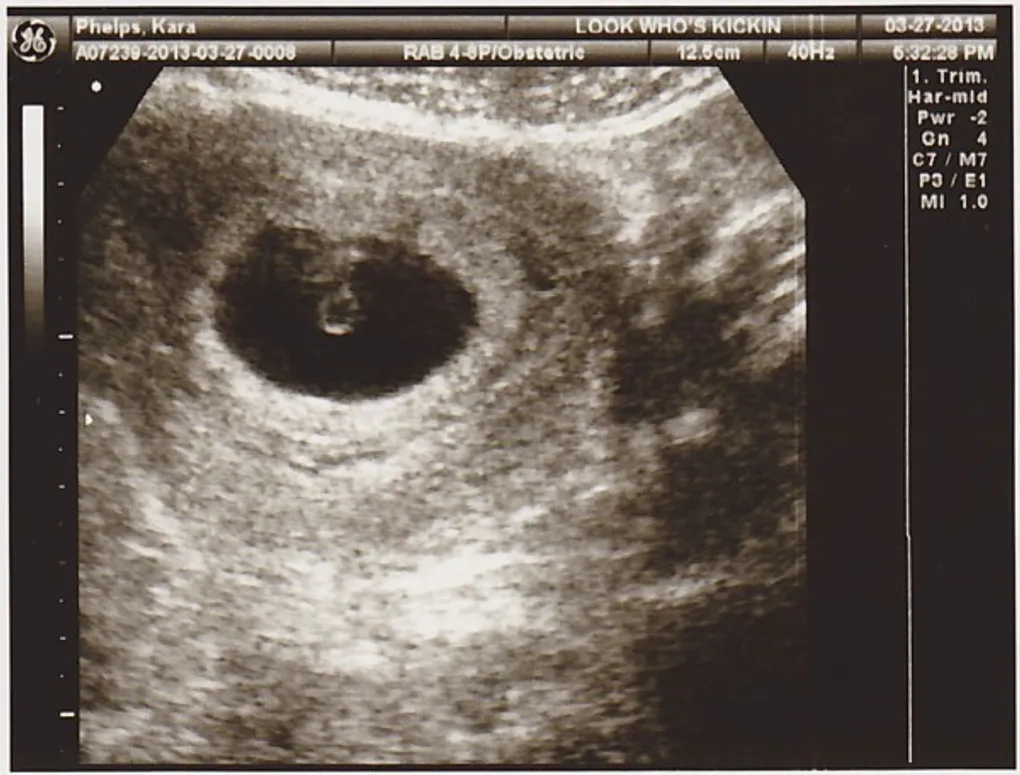

We're Having A Baby...!